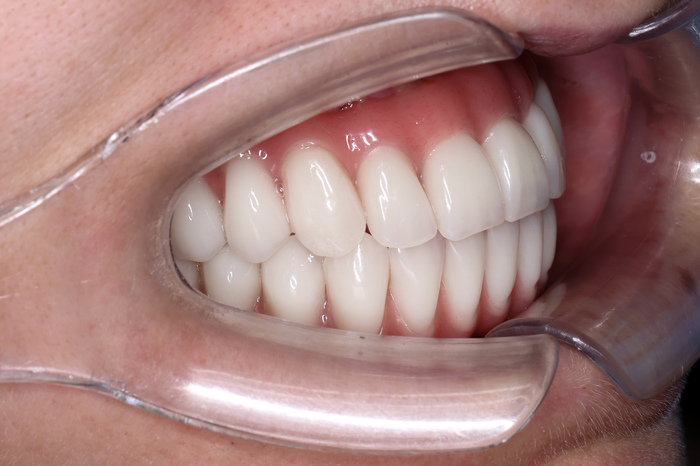

Доктор установил ей постоянную конструкцию All-on-6 с немедленной нагрузкой за 3 дня на обе челюсти.

Стоимость: Восстановление зубов по методике All-on-4 с постоянной зубной конструкцией - 499 000 руб за 1 челюсть под ключ!

Теперь Елена улыбается без стеснения и со смехом вспоминает то, как волновалась в самом начале.